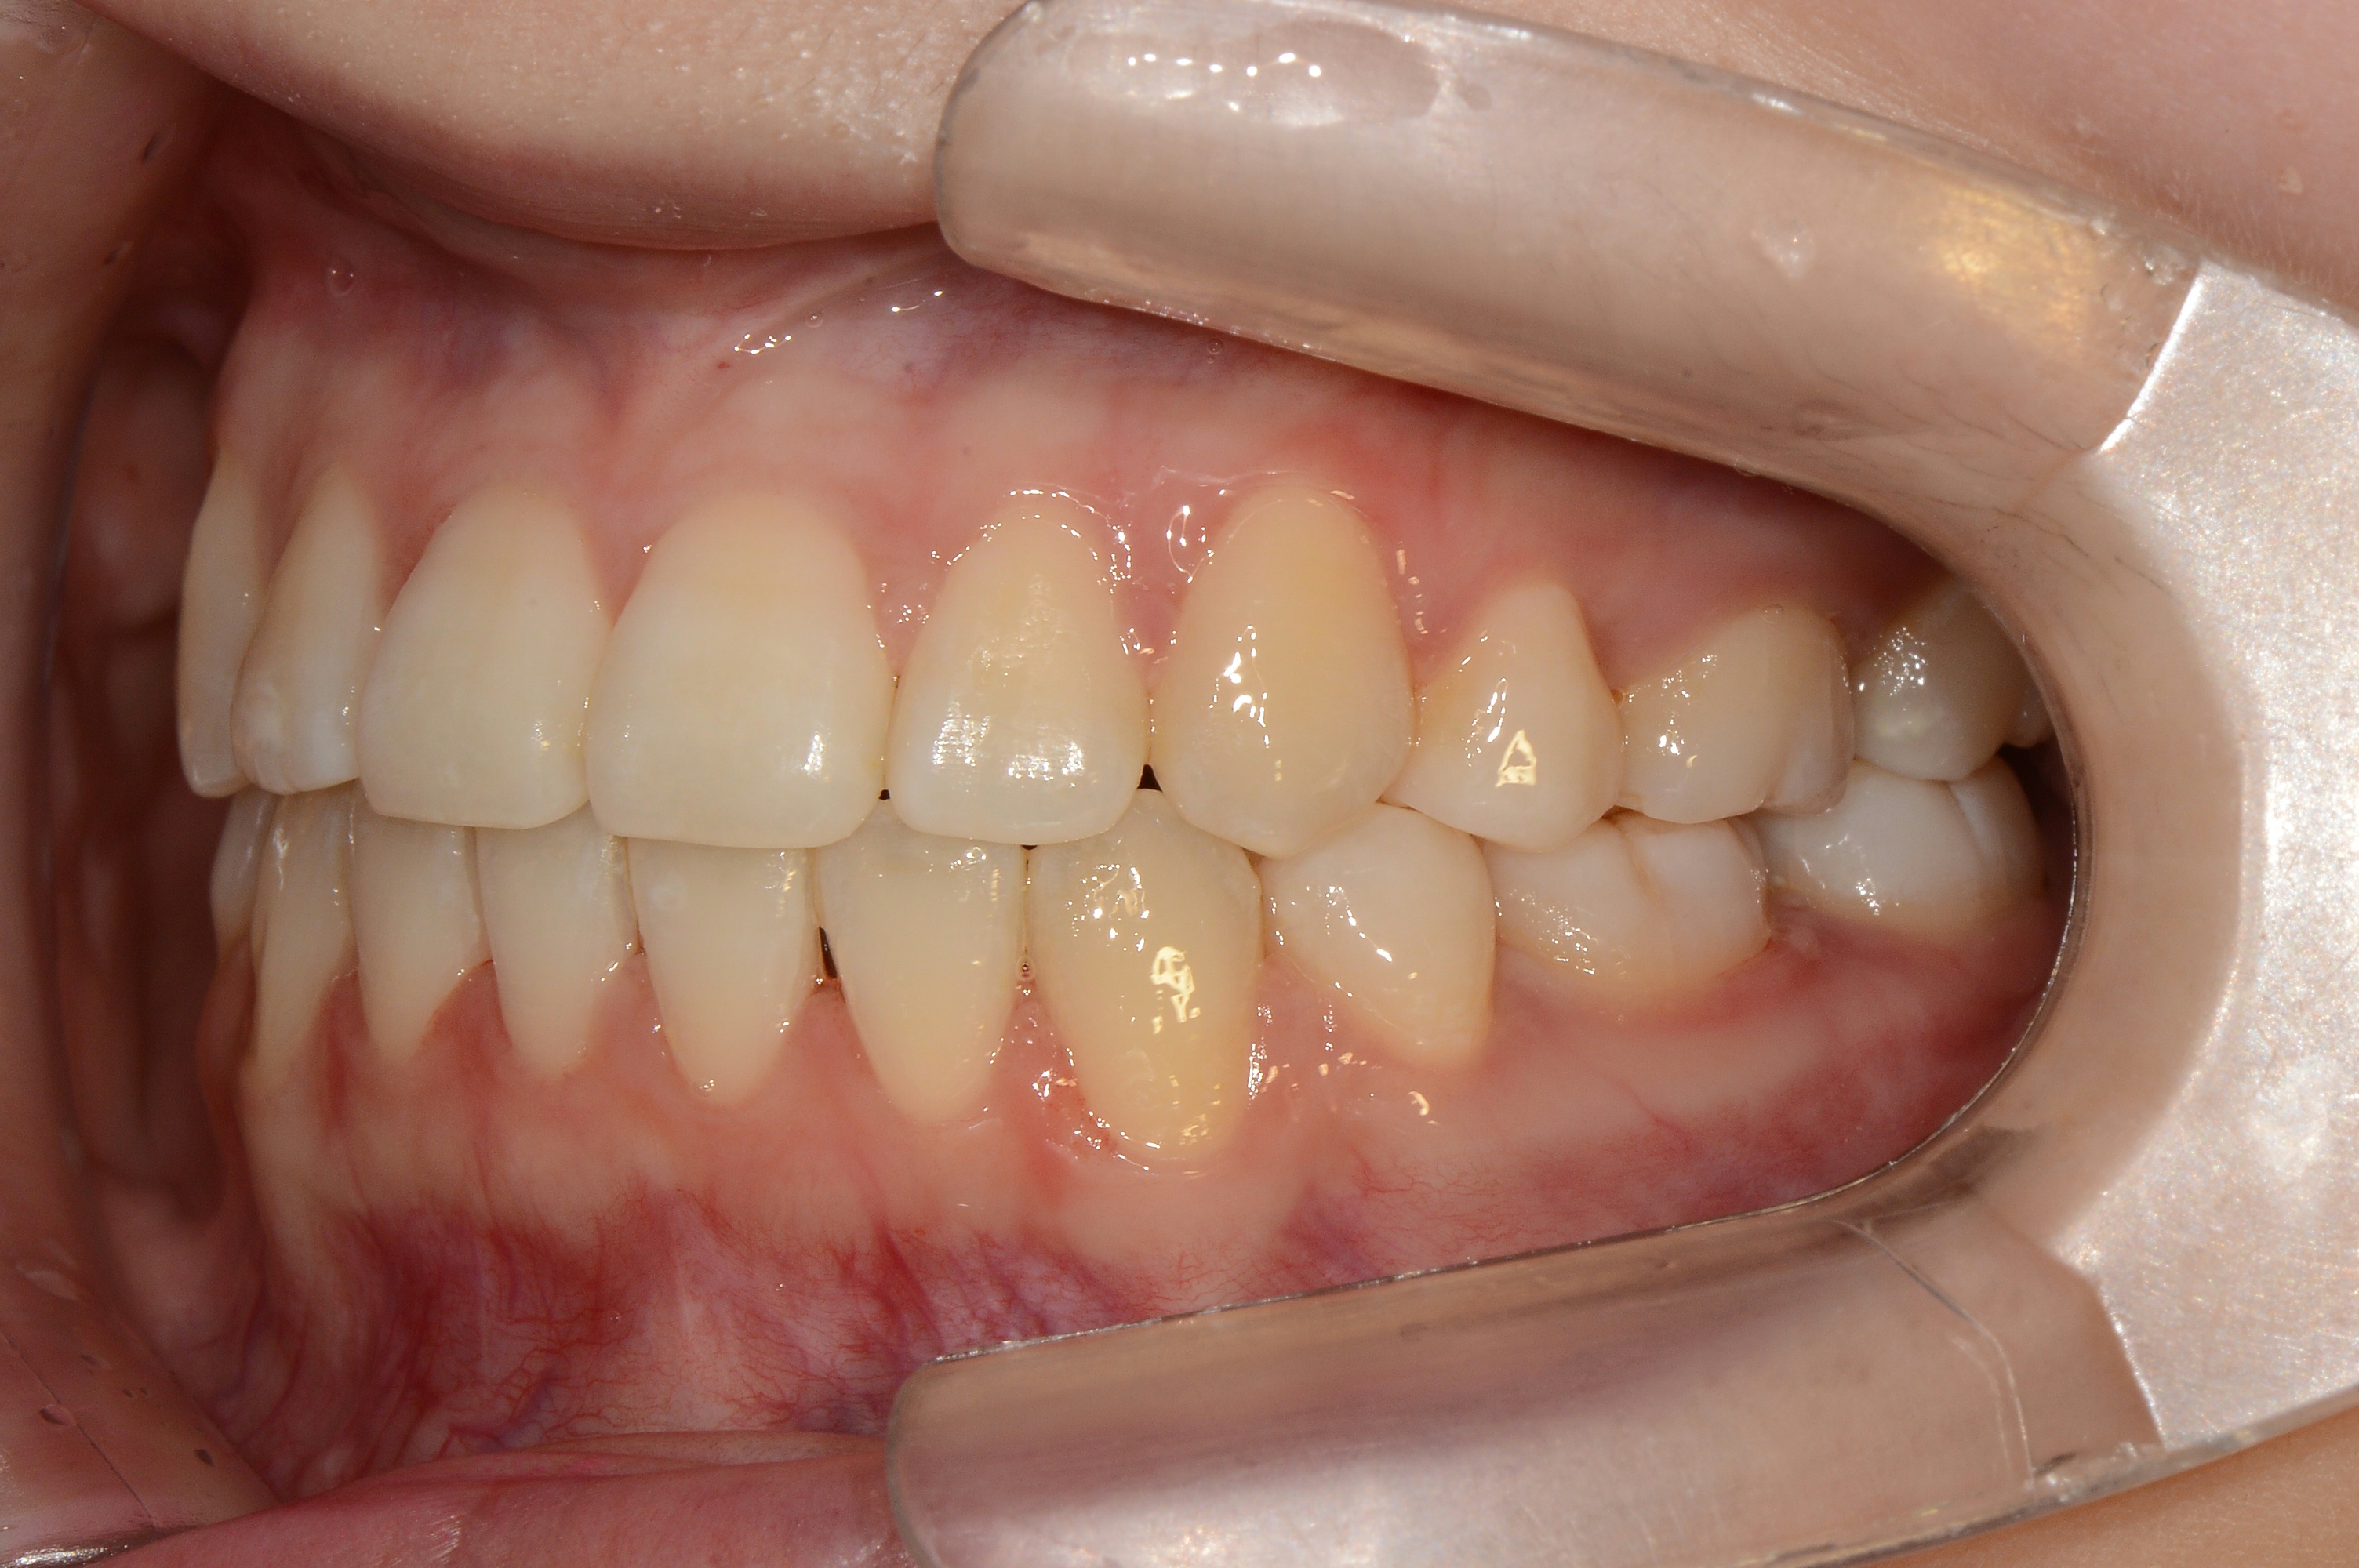

치료 전 사진입니다.